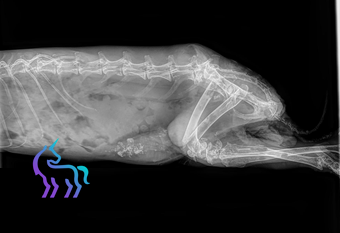

La stérilisation chez la lapine implique le retrait non seulement des ovaires, mais également de l’utérus. Cette intervention, appelée ovario-hystérectomie, est plus lourde que la simple ovariectomie pratiquée chez les chattes.